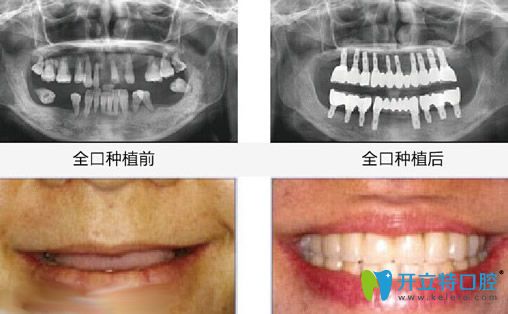

昆明竹子口腔怎么樣?國(guó)醫(yī)生All-on-4即刻種植牙案例效果來見證:

種植前:牙齒幾乎掉完,只剩下殘牙根;

種植后:無論是咀嚼力度,還是外觀都和真牙一樣。

昆明竹子口腔<!--<i data=20240703-sp></i>-->國(guó)醫(yī)生全口種植牙案例效果